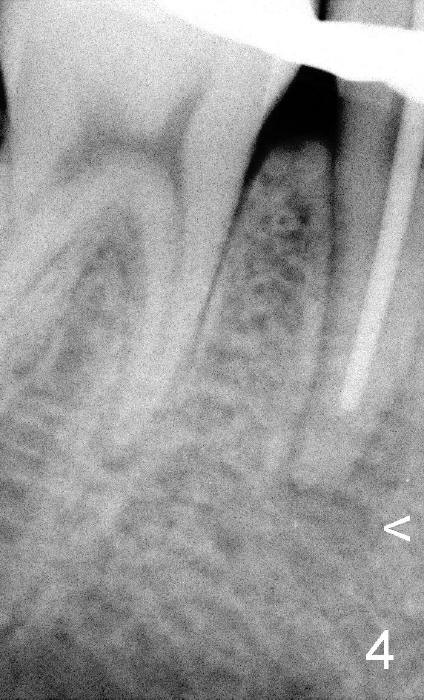

上集发表时,还没有见到病人,这集回答卢红医师疑问(下面)。今天病人来诊所诊治,他没有任何症状,右下五号牙根尖瘘道(图一箭头)是以前牙齿矫正医生发现的,咬合面中央隆起(图二箭头),后者中心好像有个小开口。对侧仿佛没有同样病变(图三*:左下五)。按照方柄忠大夫建议,根管治疗前做活力测试(Endo Ice):右下五的确死髓,有轻度扣痛。